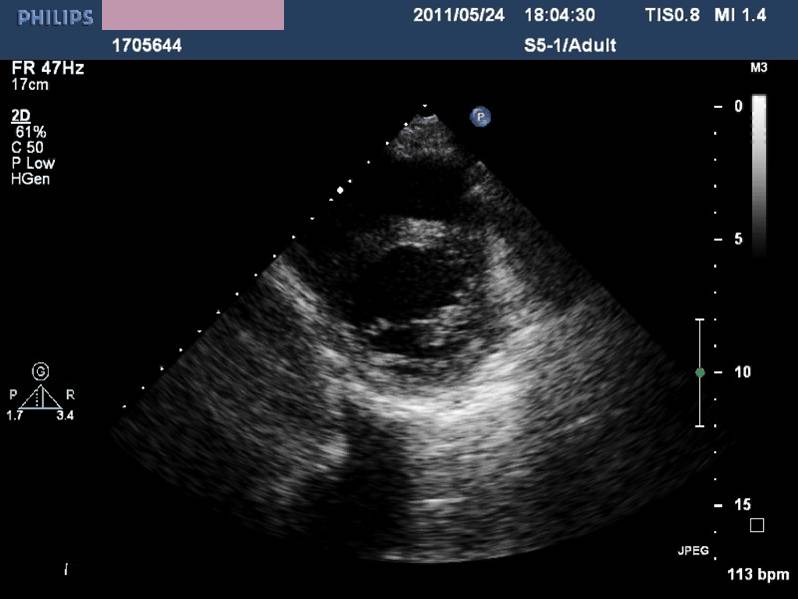

——各房室内径正常,左室收缩功能及室壁运动未见异常,LVEF 72%,少量心包积液(入院后1周)。

诊治经过-第二次心脏超声

◆一周内完全恢复

——病毒性心肌炎?

应激性心肌病?